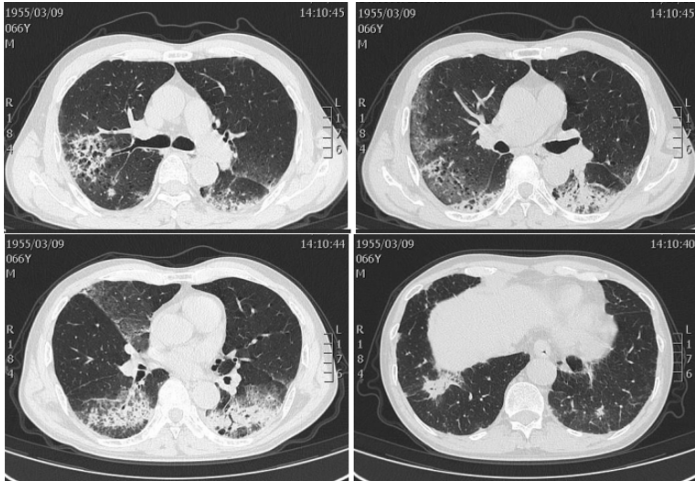

军团菌肺炎的影像学表现不具有特异性,实变是其常见的影像学发现,相对特异性的表现为磨玻璃影中混杂着边缘相对清晰的实变影,各个肺叶均可受累,1/3的病例可合并胸腔积液。免疫抑制患者的影像学表现同样不具有特异性。前述研究回顾性复习了某一癌症中心确诊的40例军团菌肺炎病例,其中,8例表现为单发或多发结节【6例实性伴有磨玻璃晕征或空洞,2例实性结节,边界清楚,没有磨玻璃晕或空洞;6例为1~2个大结节,1例双侧随机分布的大量小结节,1例局灶性磨玻璃影伴微小结节。所有CT均显示结节性浸润,仅有4例(50%)在胸部X线检查中显示结节性浸润】,32例表现为混合性非结节性肺异常(包括肺叶实变、磨玻璃影、斑片状浸润),2例发现肺炎旁胸腔积液。下图A为70岁女性,右肺上叶实性结节伴磨玻璃晕;B为41岁女性,右上肺叶有实心结节;C为17岁男性,右中叶结节伴中央空洞,伴磨玻璃晕;D为51岁女性,舌叶结节,中心空洞,周围磨玻璃晕;E为35岁女性,右下肺叶结节和周围的磨玻璃晕;F为7岁女性,舌叶结节,中央有空洞。也有一些患者偶然发现结节状军团菌肺部感染,症状不明显。我科确诊的一例军团菌肺炎患者,男性,66岁,“咳嗽咳痰伴发热2周”,每日游泳,可能与污染水接触有关,影像学以渗出样改变为主。治疗过程中出现实变、多发结节样改变。军团病的诊断需要借助于有效的检测手段。常用的检测方法包括常规培养、尿抗原检测、核酸检测。培养仍然是诊断军团菌肺炎的“金标准”,但该方法具有滞后性,可能会延误诊断。尿抗原是作为一线的诊断测试,能够快速诊断,使患者得到及时治疗。但尿抗原仅能检出嗜肺军团菌1组菌株,敏感性只有75%,容易导致部分患者被漏诊。核酸检测费用比较高,敏感性高达90%。二代测序能为诊断提供更有效、更快捷的手段。1988年,Cunha教授率先提出了WUH评分系统:①体温>39.4℃;②CRP>187 mg/L;③PLT<171×109/L(如正常下限为125×109/L,则建议PLT<200×109/L);④Na<133 ldh="">225 U/L(339 U/L);⑥干咳(包括不咳嗽、少痰,多痰排除)。【注:每项1分,3分可能诊断,4分可能极大,5分以上确诊】